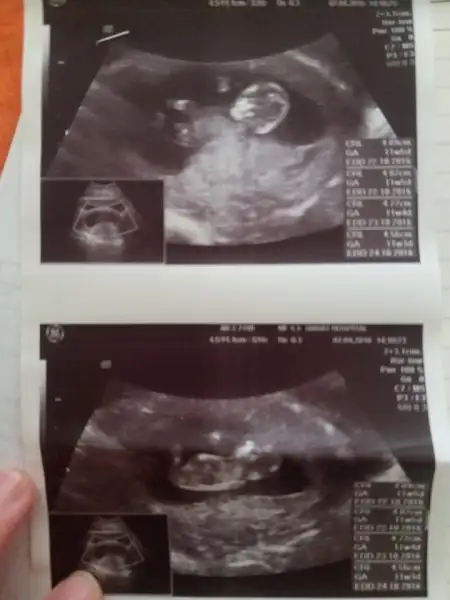

image.webp